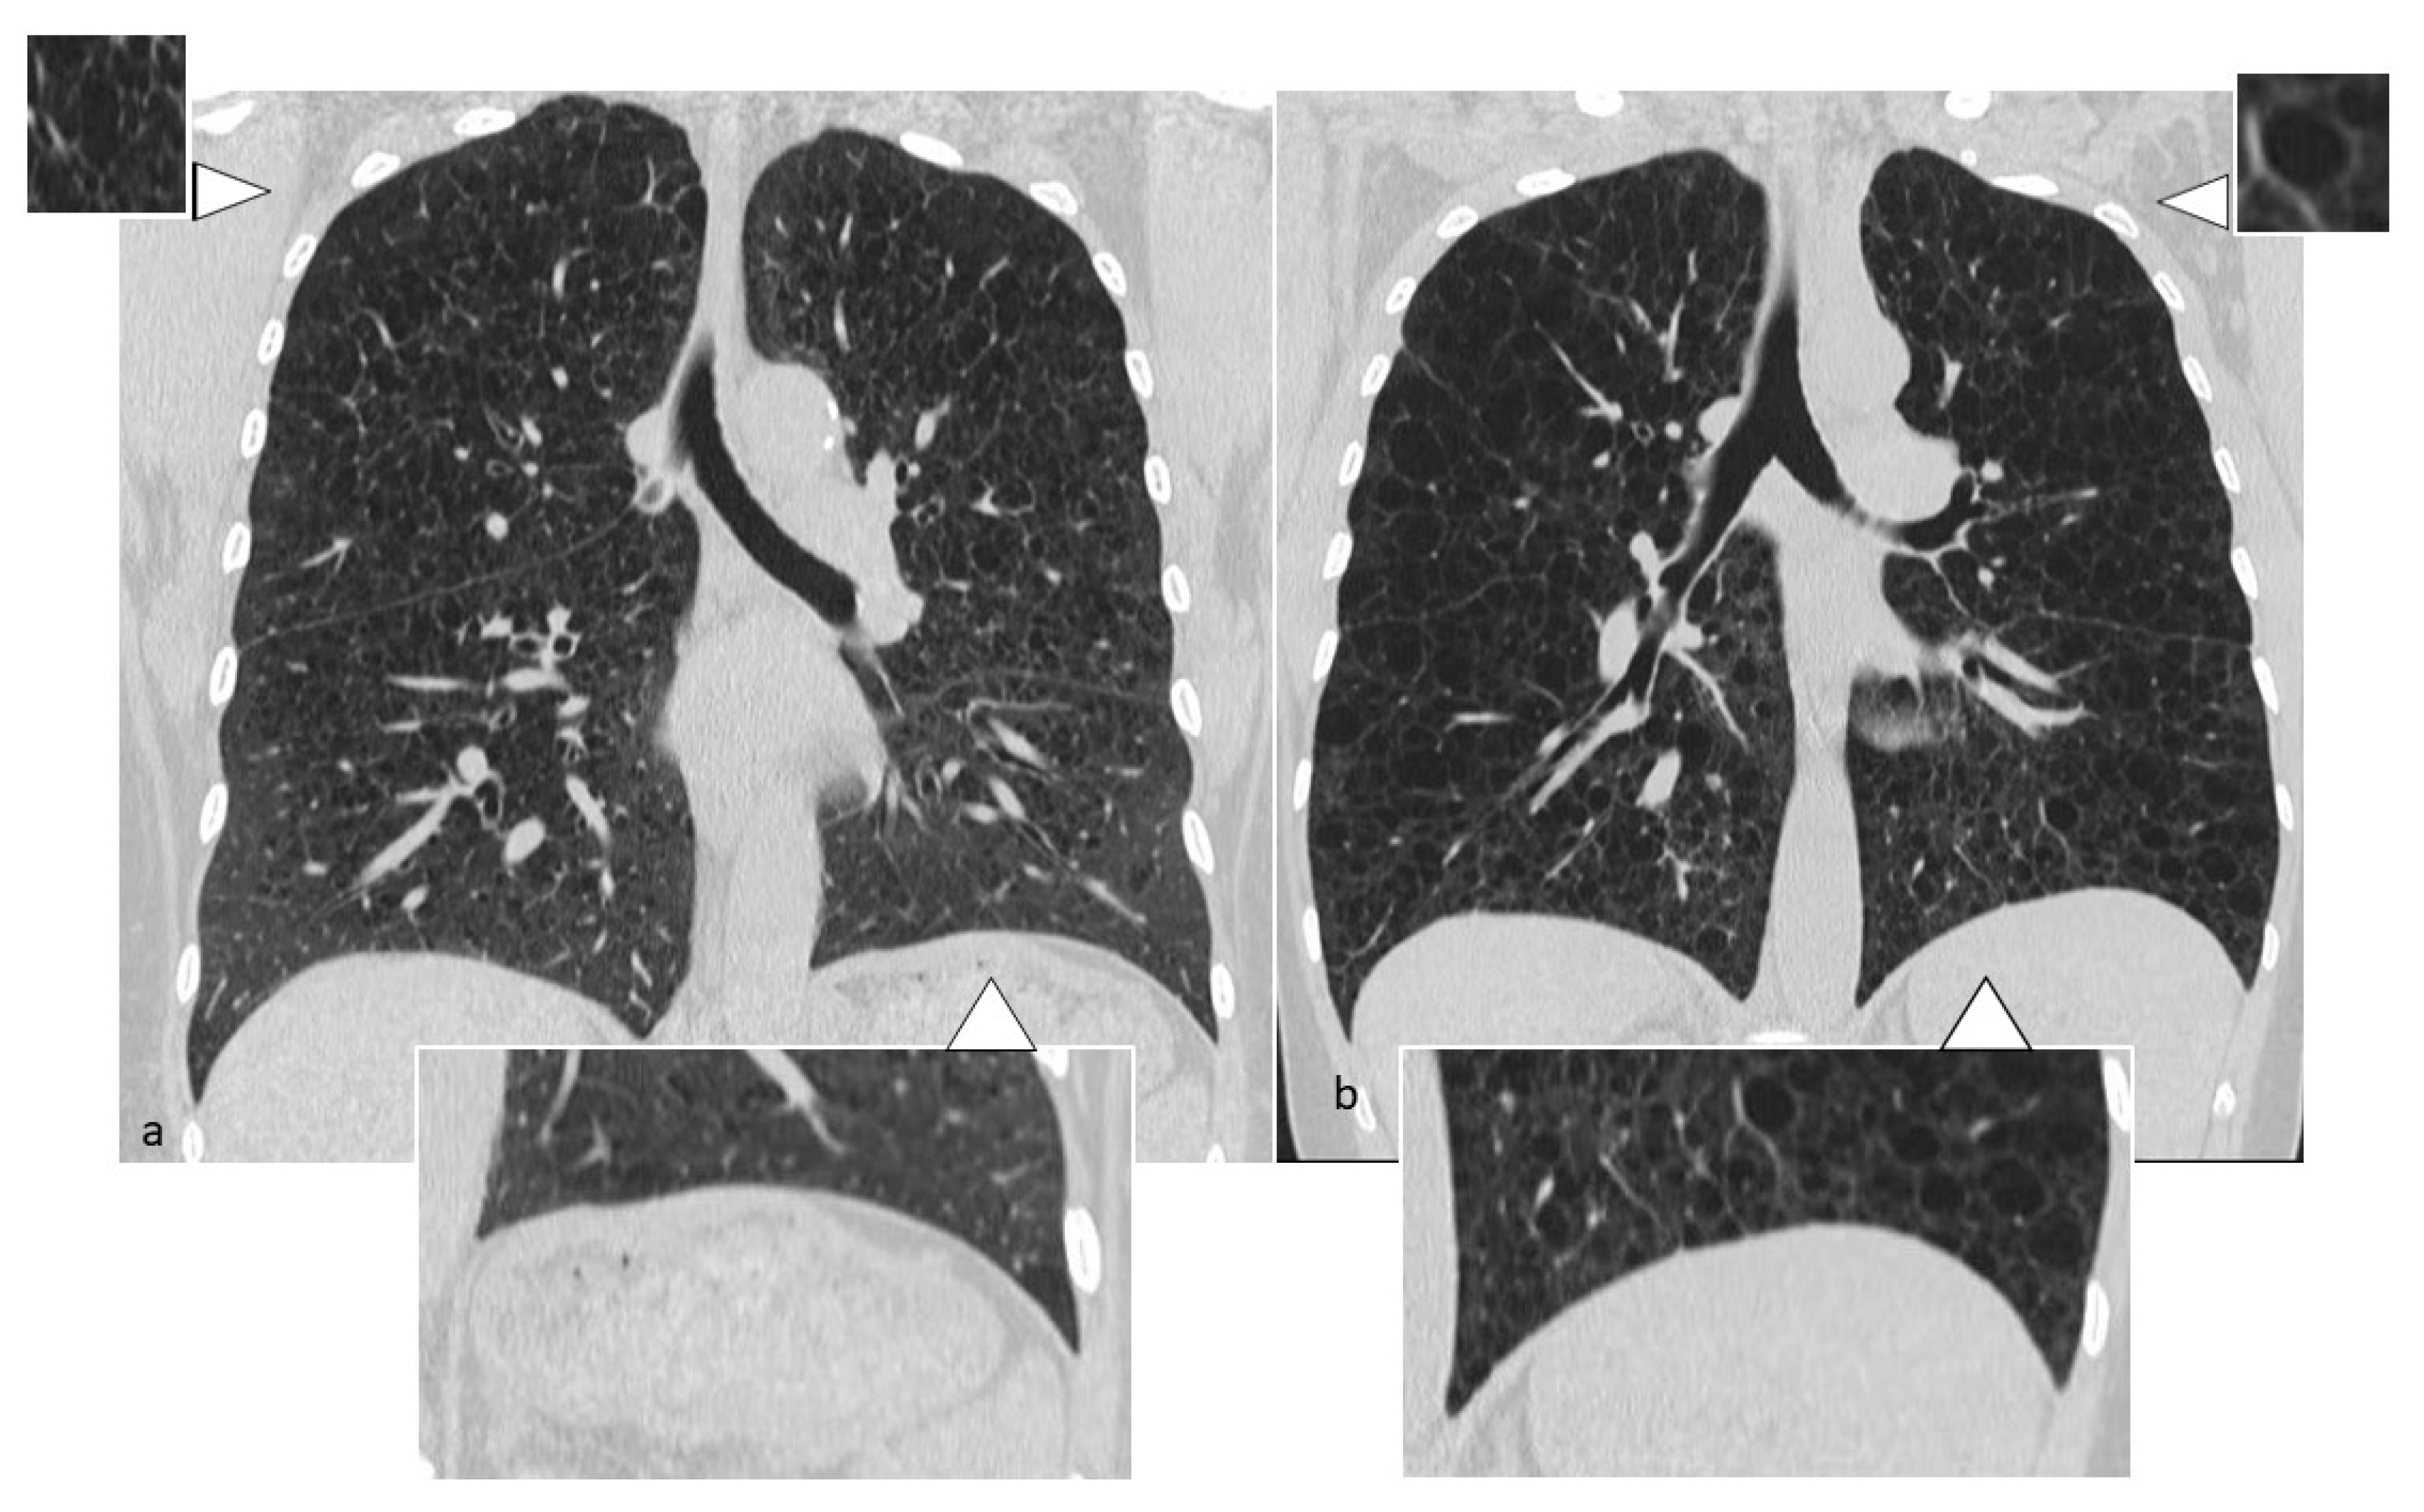

Figure 4. Differential diagnosis between LCH and LAM: in LCH (a), cysts present bizarre shape, polilobular contours and thick walls, with sparing of costophrenic angles. In LAM (b), cysts are regular and rounded, uniform in size, with thin walls; they have wide distribution, including costophrenic angles.

Lung cysts, which are the most advanced expression of the evolution of LCH, may vary in size from one to several centimeters; they occur with thick wall and “bizarre” morphology, having poli-lobulated or clover-leaf contours, in contrast to the more uniform and bland cysts typical of other diffuse cystic lung diseases, such as LAM; the cysts have also a wide distribution (Figure 2), with a predominance in the lung apices and the medium regions, typically sparing costophrenic angles (Figure 3); this distribution is one of the diagnostic keys that distinguishes LCH from LAM [10] (Figure 4). Another helpful clue is the sparing of the medial tips of medial lobe and lingula; lung volumes are normal or increased, an unusual appearance when reticular opacities or honeycombing occur. Frequently, cysts are the only alteration found in HRCT scans, but in most cases small nodules are also detectable.

LAM occurs mostly in women of childbearing age, usually between 17 and 50 years, probably related to the role exercised by the activity of the estrogens, even if cases of prepubertal and octogenarian patients have been also described [16]. Estrogens’ role is unclear, but recent studies demonstrate that estrogenic hormones can activate protein kinase B and favor dysregulated protein translation through up-regulation of Fra1 (Fos-related antigen 1) [17]. In LAM, the development of cysts is due to focal bronchiolar dilation, caused by the proliferation of atypical hamartomatous tumor-like muscle cells in the walls of the airways, which determines a “ball-valve” effect; the progressive amount of cells into the walls narrows the lumen, leading to increased pressure, and then to dilation of bronchioles. LAM cells expand into the interstitium, in the absence of neighboring tissue invasion, but in some cases show airways, the pulmonary artery, diaphragm and retroperitoneal fat involvement, with bronchial cartilage damage, arteriolar wall destruction and pulmonary arteriolar occlusion [18]. LAM cysts are typically rounded in shape, with thin walls (Figure 5), variable diameter (small: 2–5 mm; intermediate: 1–2 cm; large: >2 cm) and ubiquitous distribution (Figure 6 and Figure 7). In later stages of the disease, cysts become larger and sometimes coalescent. Unlike LCH, the costophrenic angles involvement is pathognomonic, and there is sparing of the apical regions [19] (Figure 3); in addition, the adjacent lung parenchyma is normal, although areas of superimposed ground-glass opacities, secondary to alveolar hemorrhage or lymphatic congestion, are frequently detected [20]. Lung nodules are typically absent in LAM, a feature that helps to distinguish it from LCH. The diagnostic criteria—according to the 2016 guidelines—include characteristic HRCT findings plus at least one of the following: [21]: